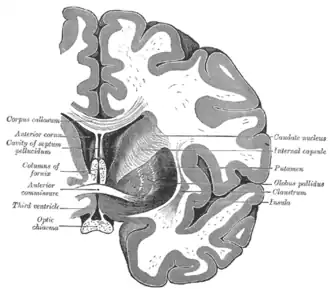

De nucleus caudatus[2] of staartkern[3] (Latijn: nucleus = kern; cauda = staart[4]) is een van de structuren van het corpus striatum in de hersenen van de mens en veel diersoorten. Lange tijd werd gedacht dat deze structuur, die deel uitmaakt van de basale kernen,[5] uitsluitend betrokken is bij de regulatie van motorische processen. De nucleus caudatus lijkt bij mensen met de ziekte van Parkinson, een bewegingsziekte, niet langer te worden geïnnerveerd door de pars compacta substantiae nigrae.[6] Uit recentelijk onderzoek blijkt echter dat de staartkern daarnaast ook een belangrijke rol speelt bij het leren en herinneren, met name voor het verwerken van terugkoppeling. Verder maakt de nucleus caudatus deel uit van het beloningssysteem van de hersenen en van de cortico–basale ganglia–thalamische lus.[5]

Anatomie

Samen met het putamen vormt de nucleus caudatus het striatum dorsale, dat functioneel als één structuur wordt gezien. Anatomisch gezien worden de twee gescheiden door een belangrijke baan van witte stof: de capsula interna. De nucleus caudatus bevindt zich in beide hersenhelften, aan de wand van de zijventrikels en schrijlings op de thalamus.[7] De boogvormige kern heeft een dikke kop en loopt steeds dunner uit in een soort staart, waaraan de structuur haar naam te danken heeft.